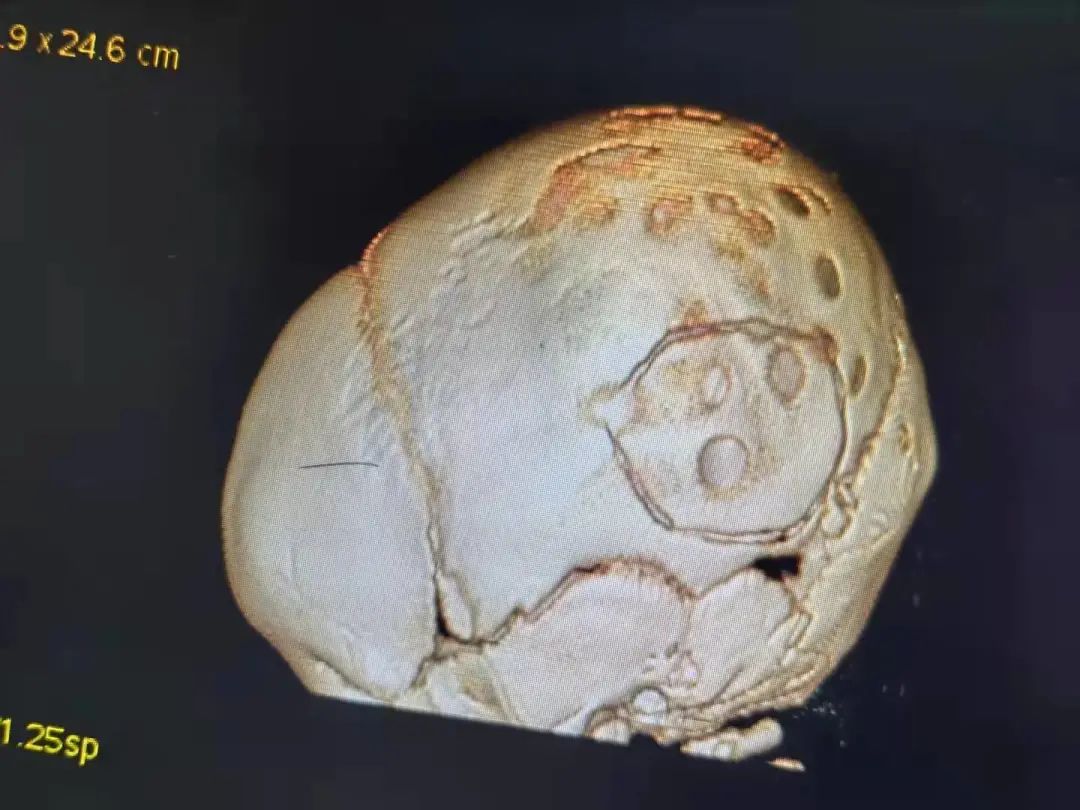

六六手术前脑部影像图

检查显示,六六虽然才三四个月大,头围已经达到了48CM,相当于两三岁的孩子的头围。颅内肿瘤的直径已超过5.5CM,就如同脑袋中被塞进了一个大鸭蛋。

六六头部骨骼也因为颅内高压出现坑坑洼洼的圆形凹陷